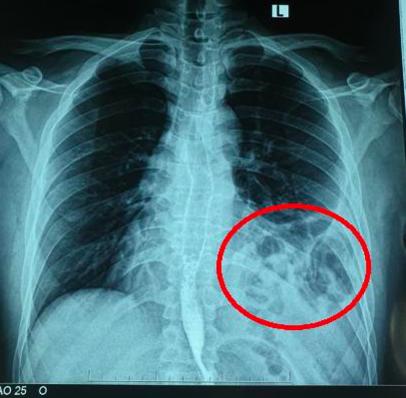

Tuy nhiên, sau khi chụp X.quang ngực phát hiện có hình bóng hơi của ruột ở trên ngực trái. Làm thêm thăm khám, xét nghiệm cận lâm sàng và hội chẩn các chuyên khoa, chụp cắt lớp khẳng định có thoát vị tạng bụng qua cơ hoành lên ngực trái.

Bóng khí của đại tràng ở trên ngực trái trên X - quang